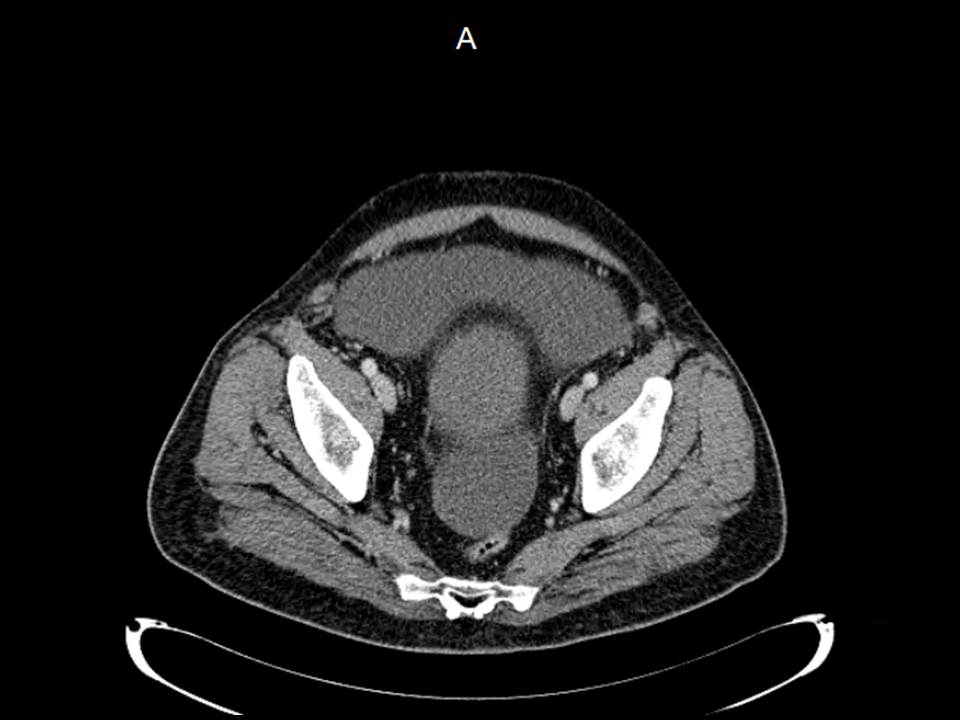

Femenina de 31 años

Dolor en hipocondrio derecho